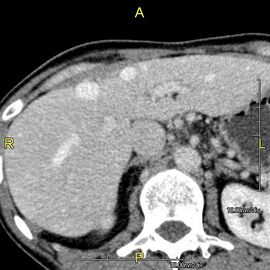

صورة مقطعية محورية تظهر أوردة كبدية شاذة تنتشر على السطح الأمامي تحت المحفظة للكبد.[73]